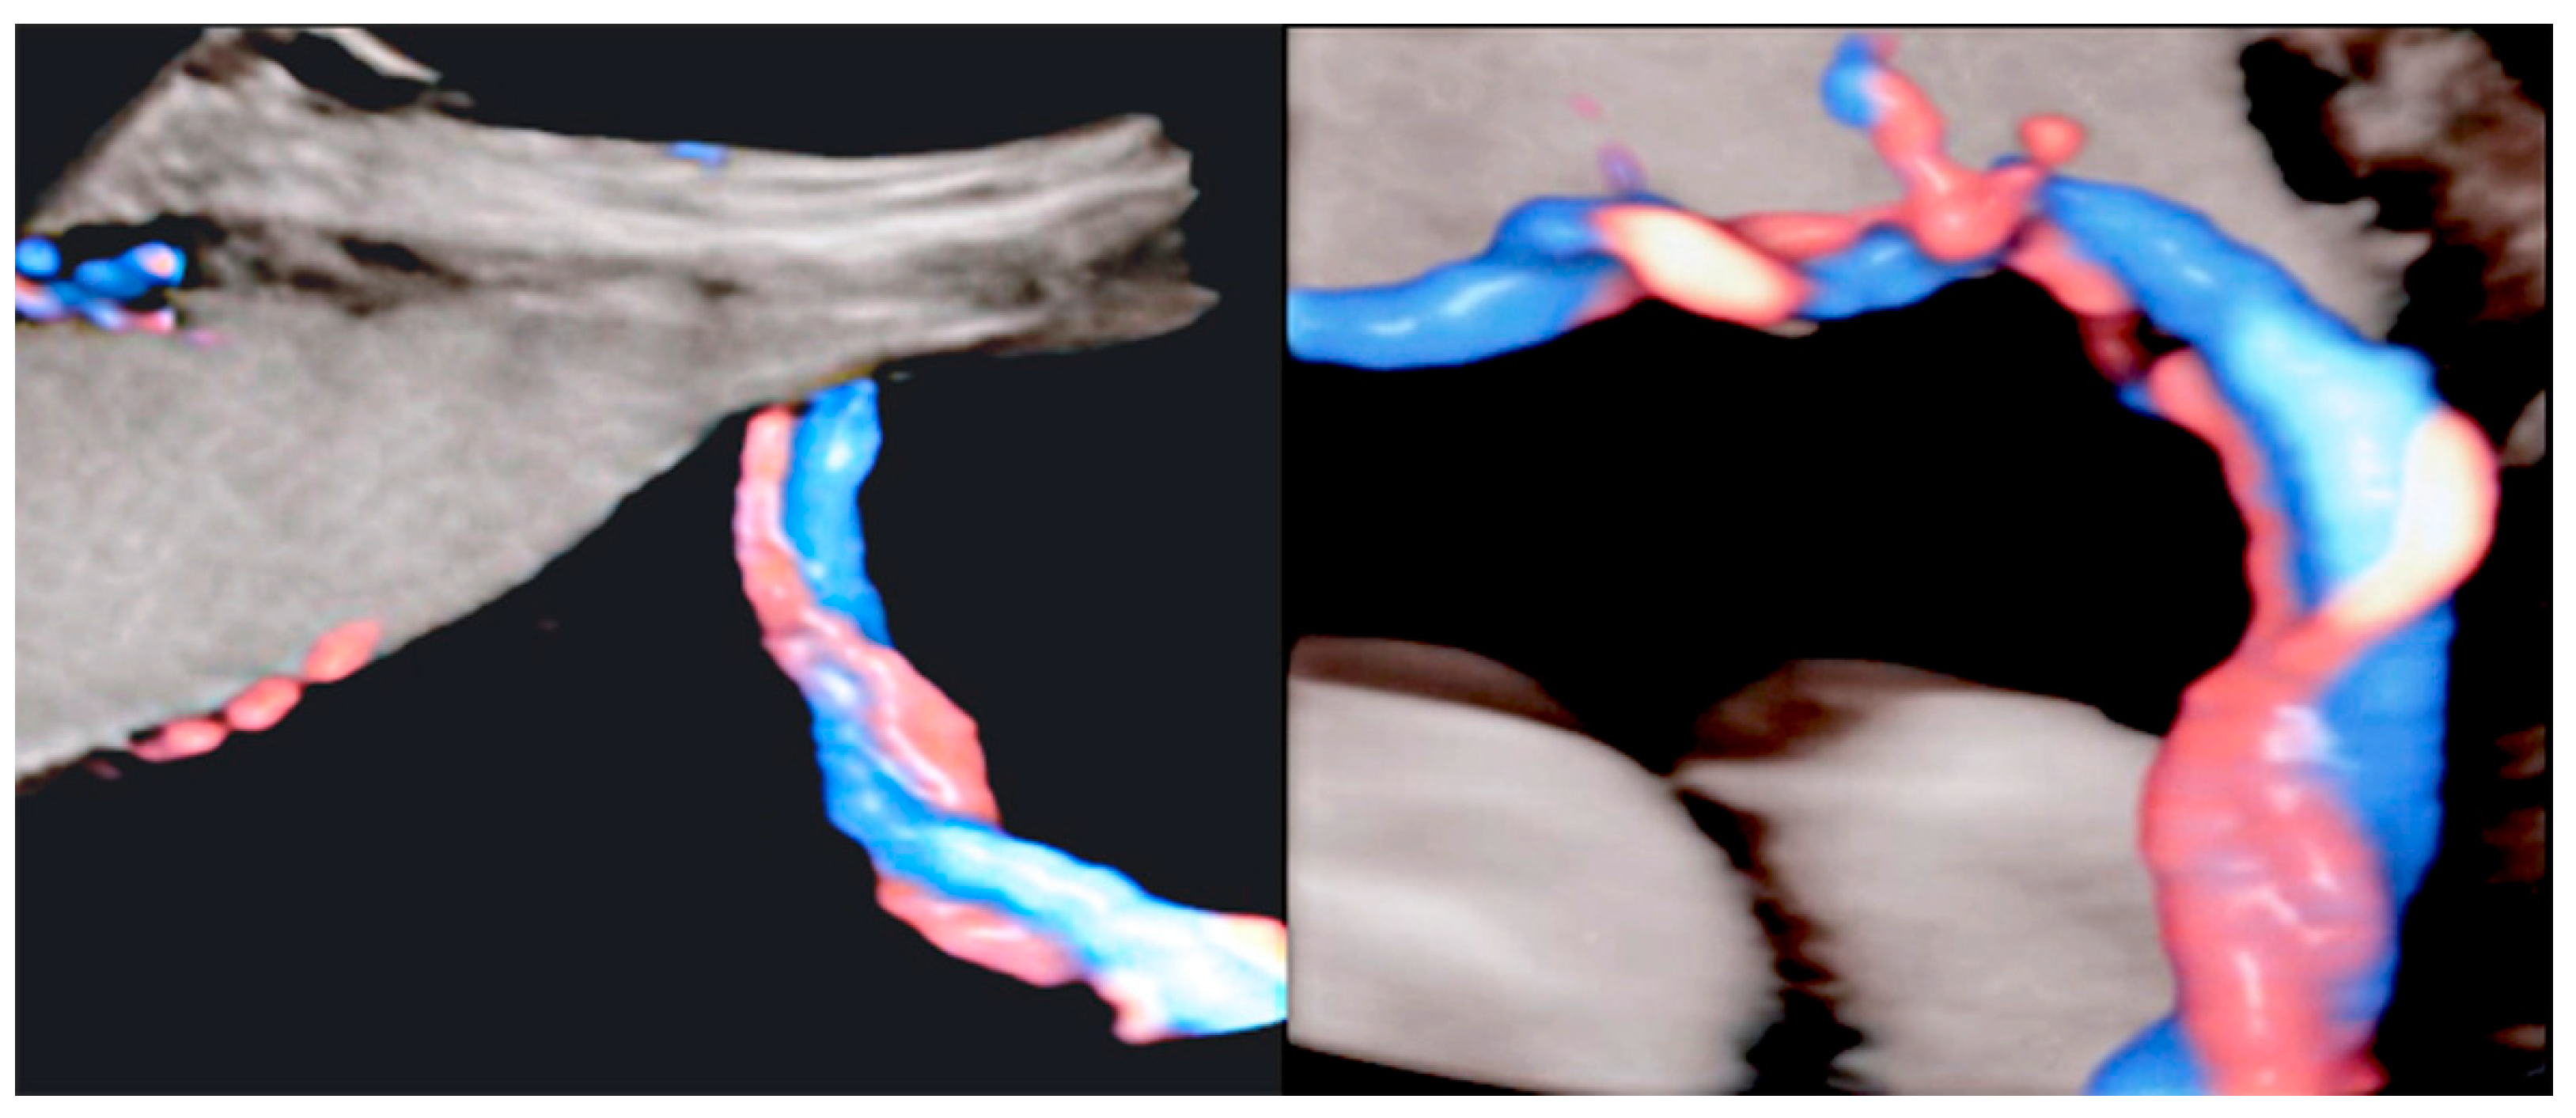

Figure 24.

Furcate umbilical cord insertion using two-dimensional ultrasound (A) and three-dimensional ultrasound (B) with HD-Flow™ Doppler: the dichotomic direction of the umbilical blood flow is clearly demonstrated at 17.3 week’s gestation (arrows).